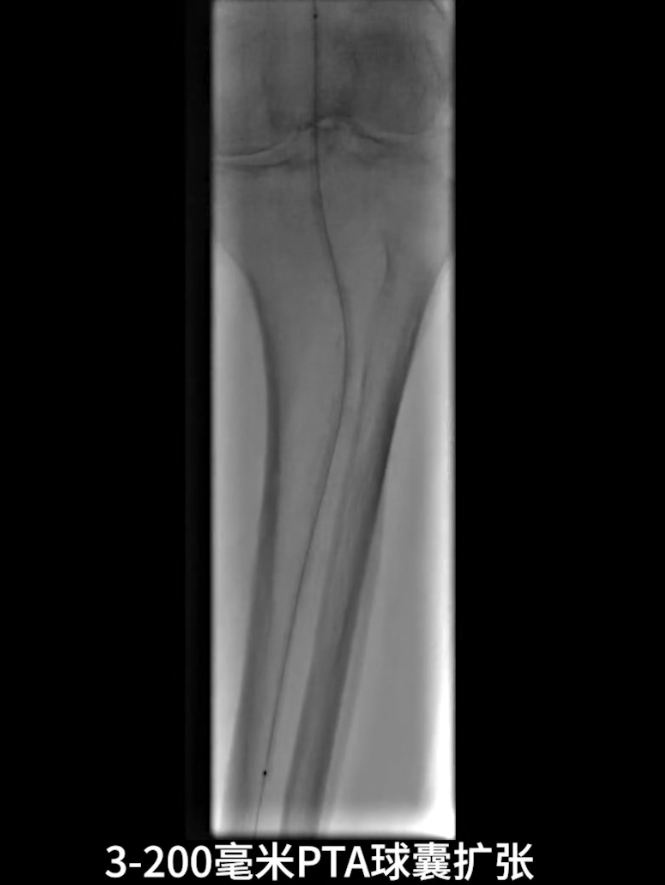

流出道扩张与优化:使用3.0×200mm PTA球囊对“胫腓干-腓动脉”全程进行扩张;

更换0.014系统导丝,经交通支选入胫后动脉远端,

再以2.0×40mm球囊扩张残余狭窄,并压迫远端逆行穿刺点止血,确保膝下流出道通畅。